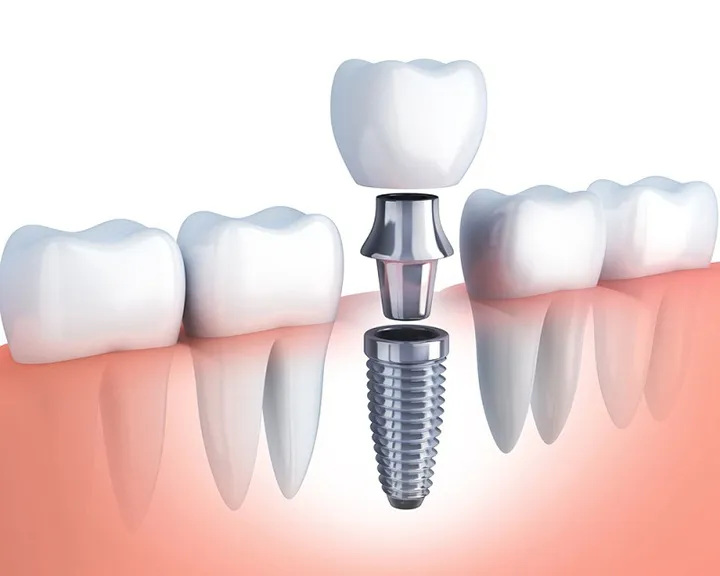

Răng sứ thẩm mỹ

Răng sứ chỉ cải thiện với tình trạng móm nhẹ, răng cửa hàm dưới vẫn cắn cân đối với răng cửa của hàm trên, những chiếc răng khác không mọc quá chen chúc.

Tuy nhiên, răng sứ chỉ cải thiện phần ngoài chứ không thể can thiệp tới cấu trúc của răng và xương hàm.